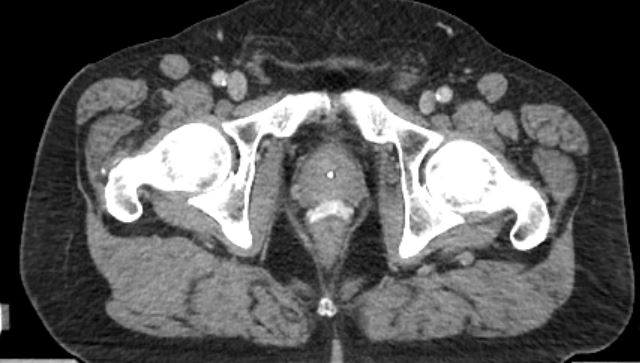

SpaceOAR Vue

kV Cone-beam computed tomography image.

First fraction. Dr. Jeff Michalski, MD (2020). Permission granted by Washington University Imaging.

For CT planning, physician-delineated prostate volume can be on average 15% smaller (under contouring) or 30% larger (over contouring) than the “true” prostate volume. With SpaceOAR Vue Hydrogel, you may be able to contour the prostate and rectum without the need for an additional MRI. This may also reduce any contouring inaccuracies, potentially leading to more accurate treatment plan creations. Accurate and consistent positioning of the patient from one fraction to the next is important to physicians, to ensure that treatment is delivered according to plan. CT radiopacity may provide an effective imaging option to MRI for patients with implanted metallic devices so you can care for a broader population of prostate cancer patients.